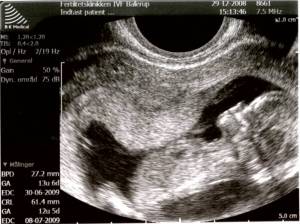

Vi var til nakkefoldsscanning igår. Selvom der var lidt rod med udregningsmetoden, betegnede lægen din sundhed som ‘strålende’.

Selve scanningen var fantastisk. Du var rigtig i vise-dig-frem-humør og lå lystigt og sparkede til blommesækken som var den en fodbold. Til at begynde med suttede du på din tommelfinger. Vi så dine arme, hænder, ben og fødder. Samt en perfekt rygrad og ribben. Vi så dig også lige forfra – og vi så din næsetip i profil. Det var fantastisk at hilse på dig!

Både far og jeg kunne have siddet i timevis og kigget på din lystige leg inde i maven.